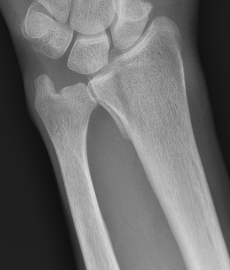

Distal Radius Angles

- radial volar tilt 11°

- radial inclination  22°

- radius is 11 mm longer than ulna

- ulna variance 2mm positive on average

Distal Radius NormalNormal Radial InclinationNormal Radial Length